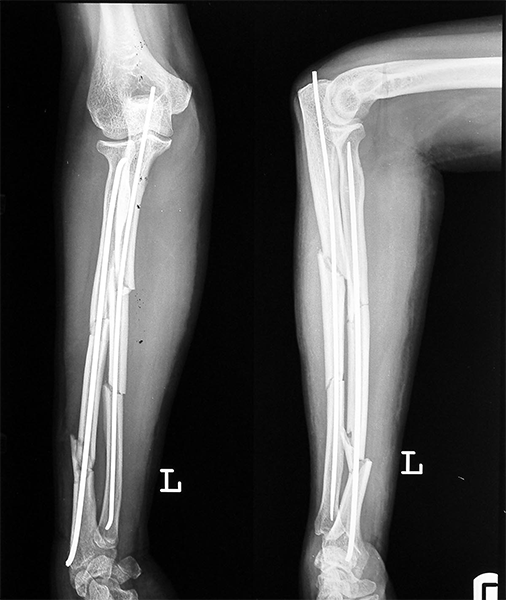

Case:6 Segmental Comminuted Fracture Radius

Patient, aged 75 years during morning walk tripped & had a fall following which he sustained injury to the left forearm. Closed reduction & interval fixation with Intra-medullary TEN nails was done in radius & ulna. Now he has full supination & pronation function of forearm.

Pre-Op

Post-Op